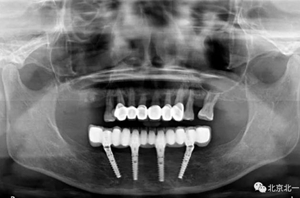

圖二十二:2015年到2016年復(fù)查時(shí)X片 ,有圖有真相

沒有假貨,貨真價(jià)實(shí),完成三年復(fù)查。

圖二十三:有圖有真相。

圖二十四:2017年11月復(fù)查時(shí)照片,植體很穩(wěn)定, 無骨吸收。